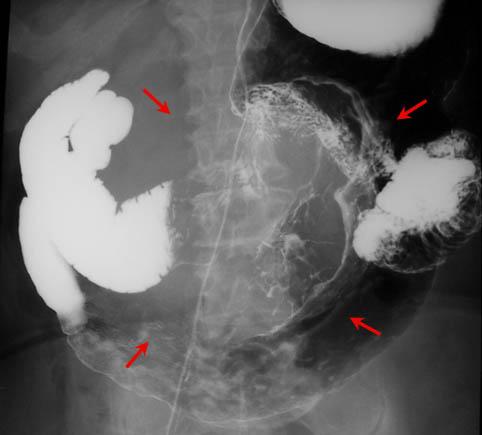

疾病(病理主体)的分类恶性非上皮性肿瘤/平滑肌肉瘤

部位(按器官分)胃(部位)/2个以上

检查方法X线

肿瘤最大直径40以上